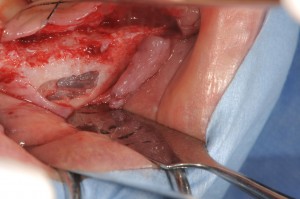

とりあえず仮の総義歯を作成して、骨のある部位に4本のBLインプラントをいれました。

前歯部には、唇側にbio-ossとbioguideでGBRを同時法で行います。

上顎結節の部位にBLのRC4.8×8mmを埋入します。

1回目の手術で4本のインプラントが入りました。